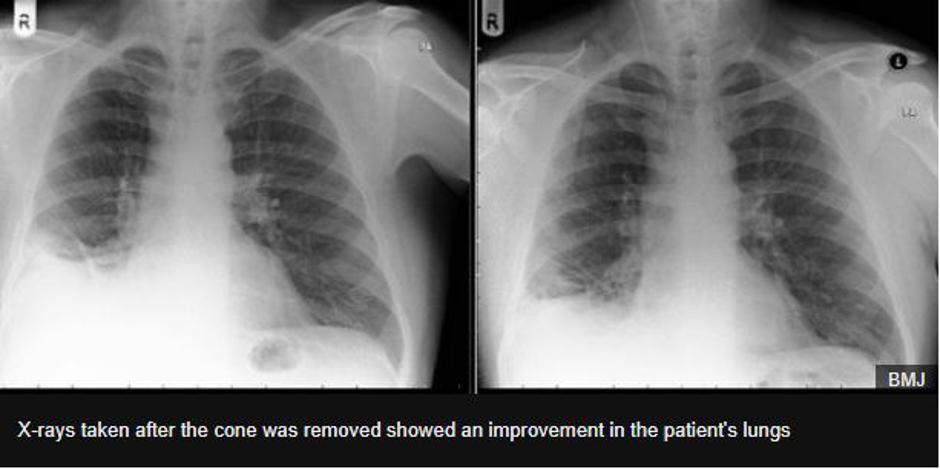

Rentgenska preiskava je pokazala na veliko senco v pljučih.

Rentgenska preiskava je pokazala na veliko senco v pljučih, po temeljitem pregledu pa so zdravniki ugotovili, da ima moški v pljučih stožec. Šlo je pravzaprav za igračo oziroma prometni stožec iz kompleta igrač znanega proizvajalca igrač Playmobil. Moški se je pozneje spomnil, da je to igračo dobil kot darilo za svoj sedmi rojstni dan.

Štiri mesece po odstranitvi drobnega prometnega stožca je bolnikovo kašljanje skoraj izginilo, njegovi simptomi pa so se znatno izboljšali, so zapisali v poročilu.

| Avtor: IBM IBM